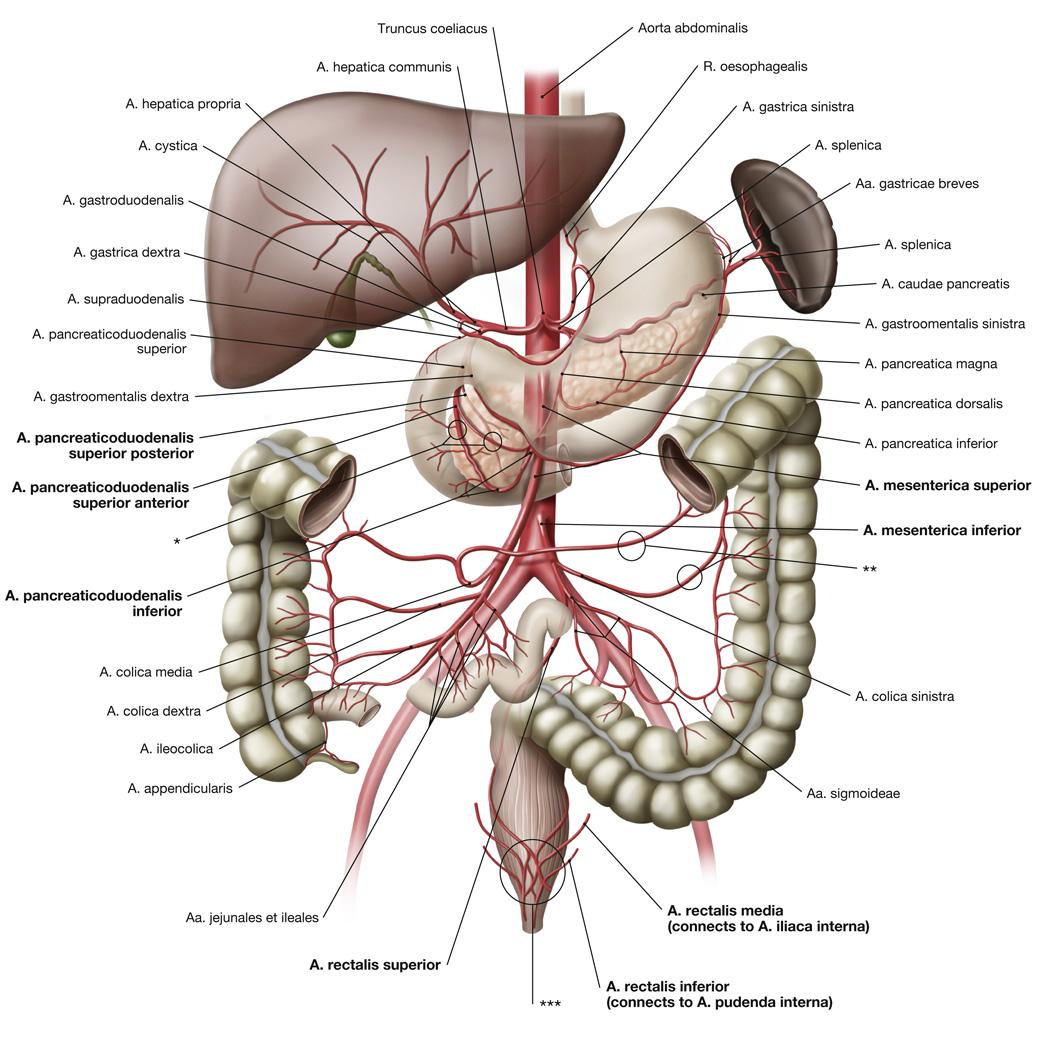

Fig 3.22: tr. coeliacus

diaphragma (groen) oesophagus -

ventriculus = maag

duodenum milt -

aorta abdominalis

|

Fig 3.23: a. mesenterica superior (AMS)

|

Fig 3.24: a. mesenterica inferior (AMI)

|

Fig 3.25: Aorta abdominalis - pare viscerale takken

|